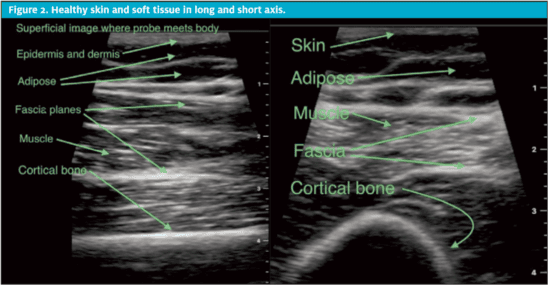

Utility Of Pocus In Skin And Soft Tissue Infection Journal Of Urgent Care Medicine